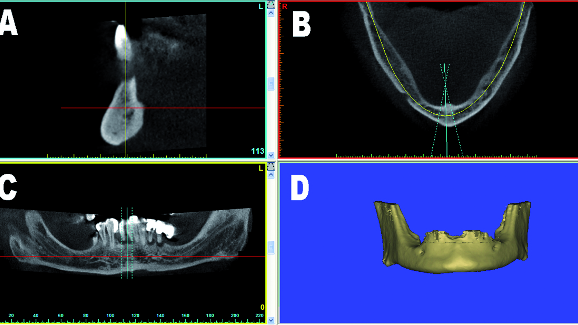

Regardless of the image acquisition process, there are four standard views that need to be fully

appreciated in the diagnosis phase. These include the cross-sectional (A), the axial (B), the panoramic (C), and the 3-D reconstructed volume (D) as seen in Figure 1. The ability to interact within these images differs from software to software. It is the ability to visualise 3-D data with improved tools that empowers clinicians to assess individual patient anatomy. The cross-sectional slice is important for the assessment of the facial and lingual cortical bone plates, the intramedullary bone, and the positioning of teeth within the alveoli. The axial view allows inspection of the entire upper or lower jaw, the maxillary sinus volume, the position of the incisive canal in the maxillae, and the mental foramina in the mandible. The panoramic view is an overall scout image, and can be helpful in tracing the mandibular nerve, and assessment of the maxillary sinus floor near the nose region. The 3-D reconstructed volumes are invaluable in the planning process and in communicating information to the members of the implant team, including the patient and the dental laboratory technician who will fabricate the final prosthesis. These images are especially useful, as they are most readily understood and appreciated.